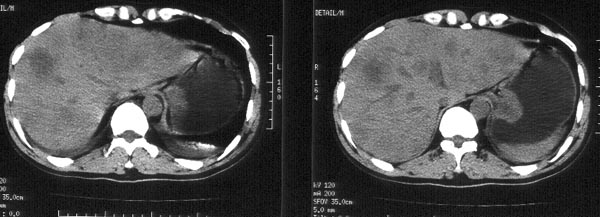

男性,46岁。腹痛月余。胃镜检查示“胃贲门区占位”,活检病理示

“胃贲门癌”。

ct平扫:胃贲门部见软组织肿物突入胃腔内,大小4x3cm,浅分叶状,中央密度较低,邻近胃壁增厚。外缘与周围组织分界清。im25层面,小网膜囊区见两枚肿大淋巴结,直径均约3cm。肝脏大小正常,肝内散在分布多个大小不等的类圆形低密度影,最大者位于肝右前叶上段,直径约4cm,病灶边缘模糊,与正常肝实质分界欠清。

ct诊断:胃贲门癌,并腹腔淋巴结转移及肝内多发转移。